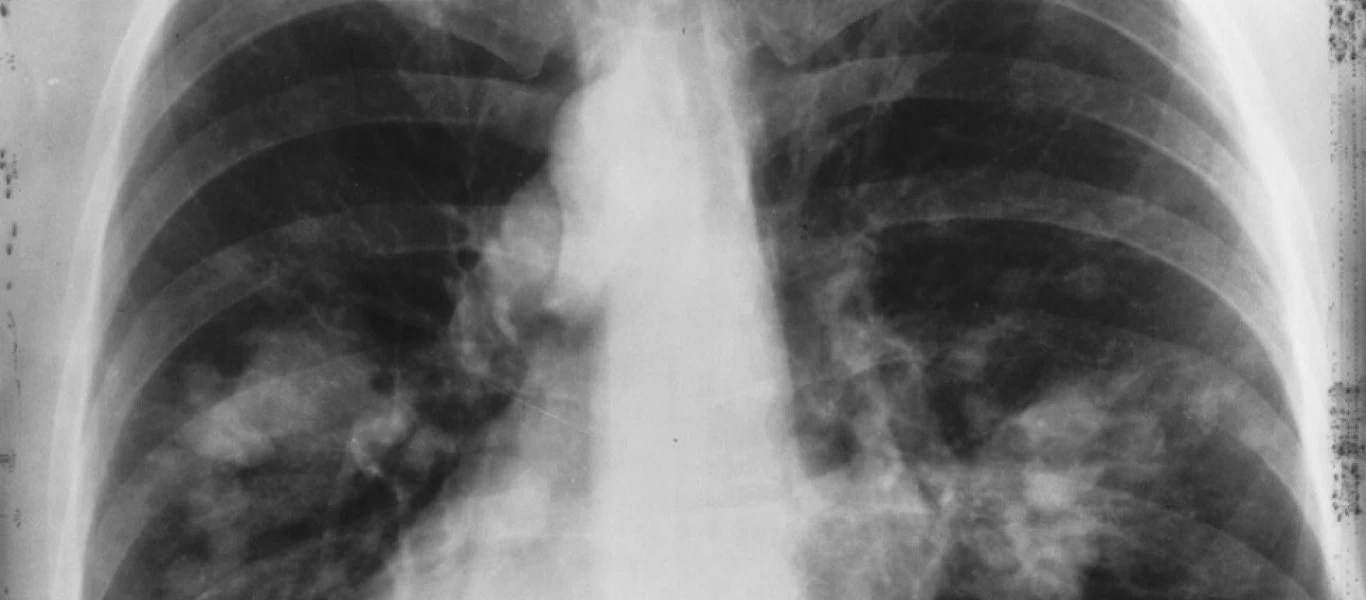

Χρόνια Αποφρακτική Πνευμονοπάθεια: Αυξάνονται σε παγκόσμιο επίπεδο τα ποσοστά

Αν και τα ποσοστά της Χρόνιας Αποφρακτικής Πνευμονοπάθειας (ΧΑΠ) έπεσαν στις περισσότερες χώρες μεταξύ του 1995 και του 2017, το συνολικό ποσοστό θανάτων από ΧΑΠ αυξάνεται σε πολλές χώρες τα τελευταία...

Η πρώτη αιτία θνησιμότητας στην Ελλάδα - Πώς θα μειωθούν οι θάνατοι από αυτήν;

Με καρκίνο του πνεύμονα διαγνώστηκαν στην Ελλάδα 9.964 άτομα το 2018, με την πλειοψηφία των κρουσμάτων (7.862) να αφορούν στους άνδρες. Πρόκειται για την πρώτη αιτία θανάτου από καρκίνο στη χώρα μας, ...